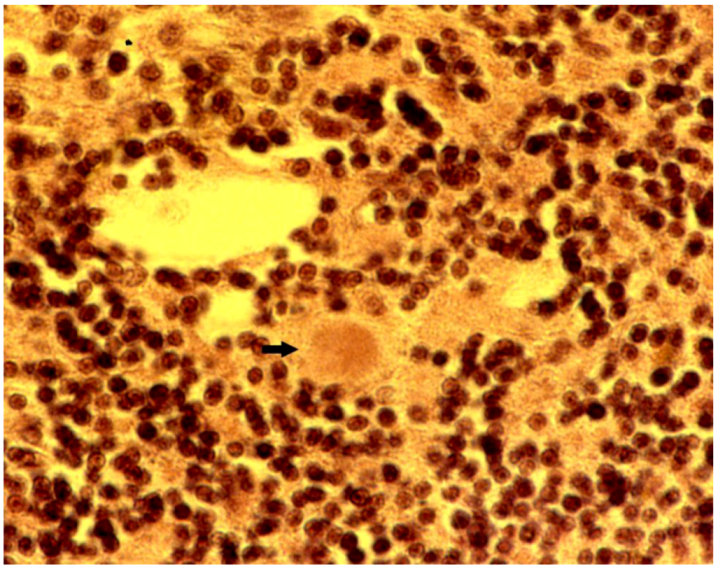

8. Neuropathology